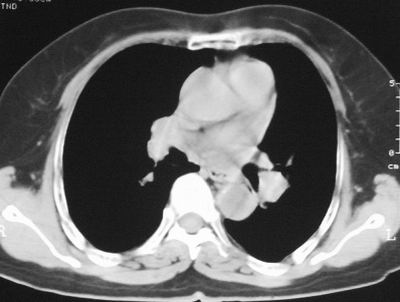

患者,女,64岁,4年前左腮腺"多形性"腺瘤手术治疗史.现复查胸部ct见左下肺块状影,该影与原左腮腺手术是否有联系?

本次复查胸部ct

我考虑炎性假瘤:1,边界模糊.2,邻近胸膜增厚,胸膜外脂肪也增厚.3,周围有肺气肿征.4,无胸水,无淋巴结肿大.

肿块周围提示慢性改变,邻近胸膜外脂肪有沉积,考虑为良性,炎性假瘤可能。